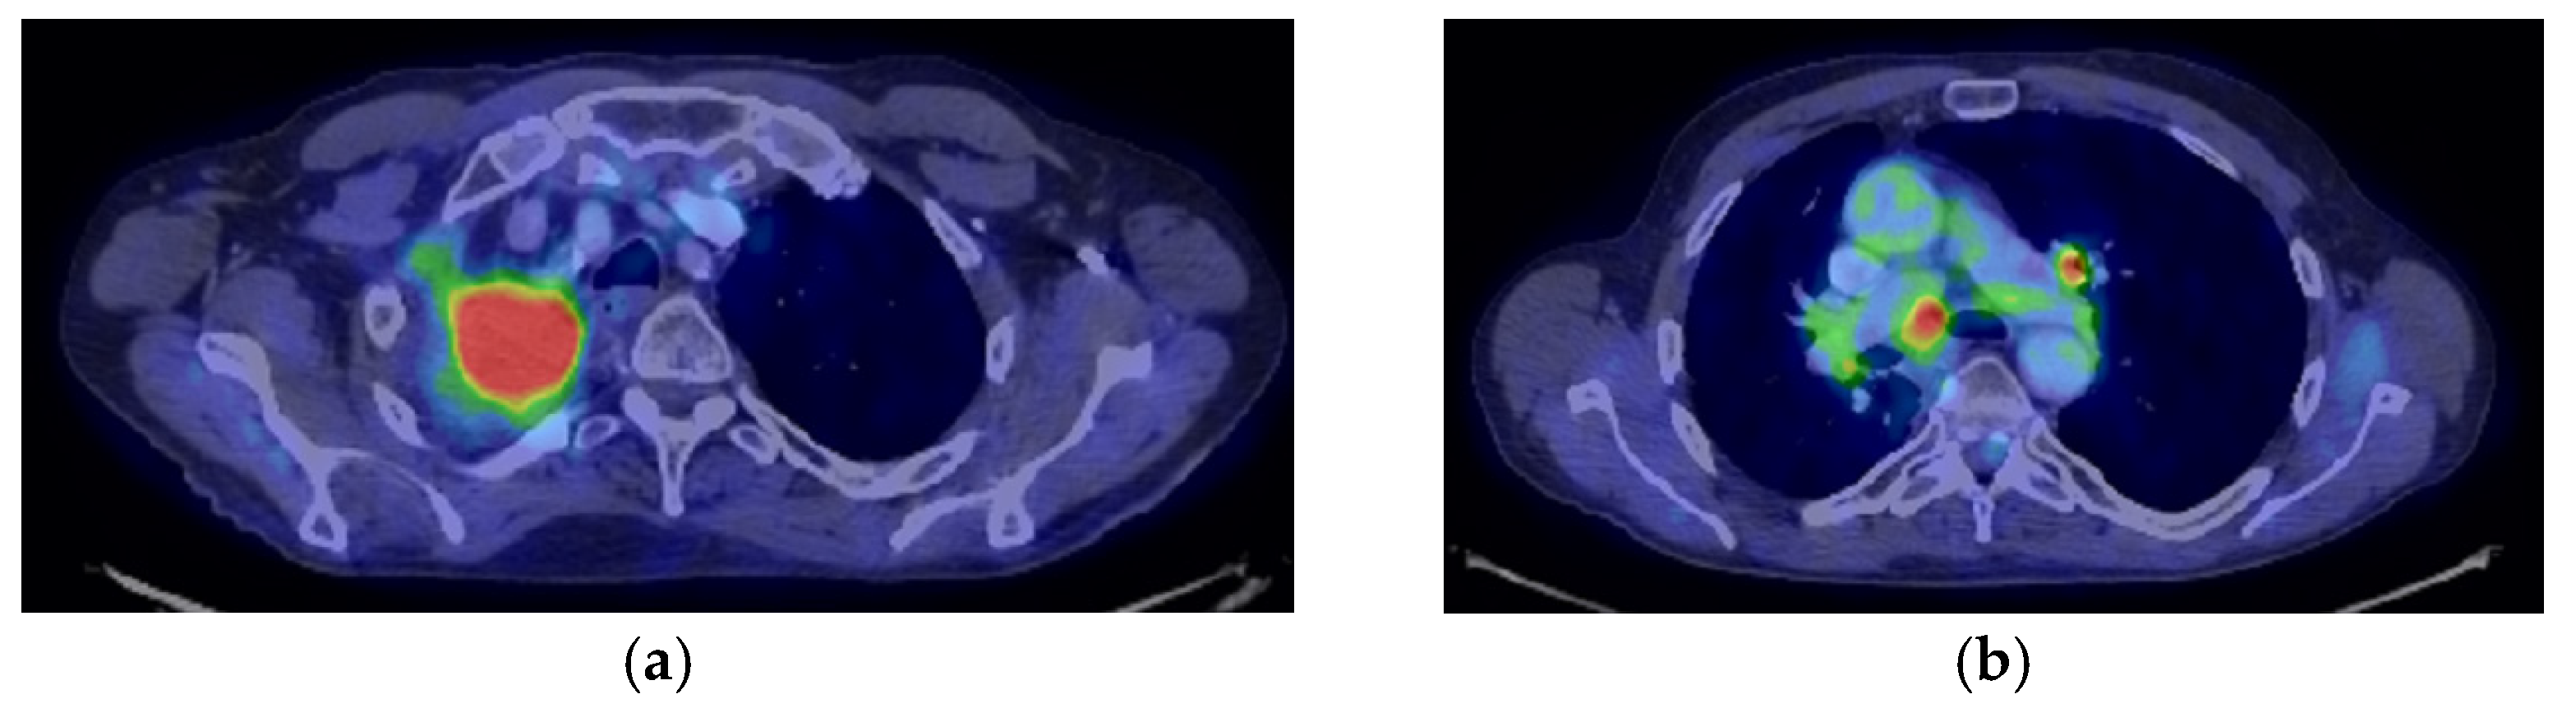

2. Case Presentation

2.1. Systemic Third-Line Therapy (4xDocetaxel) Was Initiated 04–07/2020

2.2. Monitoring 2022: Oncological Commission 1910/16.08.2022

2.3. Oncological Committee 07/25/2023 Recommended

- Consider rescue re-irradiation (SBRT), taking into account the current primary tumor dimensions of 24 × 34.2 mm on PET CT from 06/2023 and also the total dose previously administered (08–09/2020), the previously applied fractionation, the time between the two irradiations, the cellular repair time and the dose constraints for the organs at risk.